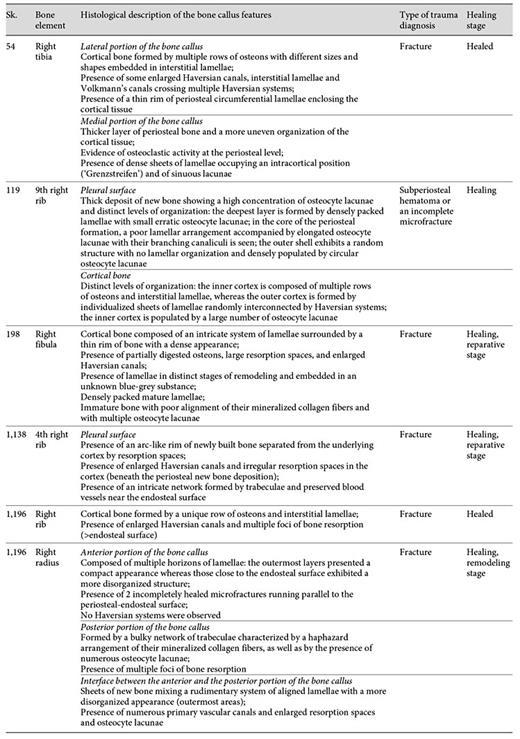

Histomorphology of the Bone Callus

The histological analysis of the 6 bone samples showed a well-preserved bone microanatomy with good bone birefringence. Some structural differences were found when the bone calluses were compared (table 4).

Evaluation of the histological features of the bone callus by individual, sample, healing stage, and type of trauma diagnosis

A remodeled callus microstructure characterized by well-defined osteons and interstitial lamellae was also identified in the right rib sample retrieved from Sk. 1,196. In this sample, multiple bays of bone resorption were observed in the endosteal and periosteal surfaces. At some points, larger areas of bone resorption enclosed by thin layers of bone lamellae were seen, in addition to enlarged Haversian canals and numerous osteocyte lacunae (fig. 7a-d). In contrast with the above-mentioned case, the sample retrieved from the right radius of the same Sk. 1,196 individual showed a more immature microstructure. For example, an intricate network of trabeculae, some of them with signs of bone resorption, was observed in the posterior side of the bone callus. The typical structure of a mature cortical tissue was recorded as absent from the core of the bone callus, as well as from the opposite anterior surface. That is, no clearly defined osteons, interstitial lamellae, and Haversian canals were observed. Instead, the anterior portion appeared to be formed by horizons of lamellar bone pinpointed by a high density of osteocyte lacunae, which suggests distinct levels of bone deposition. Irregular lines running alongside the bone lamellae were also seen. Finally, a pattern of disorganized lamellae and immature bone populated by osteocyte lacunae and separated by irregular areas of bone resorption and discrete Haversian canals was seen in the interface between the anterior and the posterior surfaces of the bone callus (fig. 8a-e1). The most striking example of an immature callus microstructure came from the Sk. 198 sample. In spite of the healed macroscopic appearance, the histological study revealed a cortical tissue formed by an intricate system of lamellae, comparable to trabeculae, in which multiple branches and islands of well-preserved lamellae connecting partially digested osteons were observed. A combination of mature lamellae with more immature bone populated by multiple osteocyte lacunae and large resorption spaces was also noticed. At the periosteal level, a rim of lamellae in distinct stages of maturation was seen bordering the outer surface of the bone (fig. 9a-d).

A complete unhealed fracture was observed on the 4th right rib of the adult male Sk. 1,138. In this particular case, the most revealing histological feature observed was the presence of an arc-like structure of new bone connected with the underlying cortex by bone pedestals. Intact endosteal and periosteal circumferential lamellae were also visible, as were remnants of blood vessels. In fact, a network formed by rib trabeculae and preserved blood vessels was observed on the endosteal surface. Enlarged Haversian canals and irregular resorption spaces were visible at the cortical level (fig. 10a-c1).

a Micrograph of the Sk. 1,138 rib cortical tissue presenting mature osteons and enlarged Haversian canals (white arrowheads) and a deposit of new bone with an arc-like microanatomy at periosteal level (white asterisks). Note the presence of rib trabeculae and preserved blood vessels (black arrowheads). b Another view pinpointing a major area of osteonal bone resorption (white arrowheads) and the newly built bone (white asterisks). c, c1 Bone segments showing massive foci of osteon resorption (white arrowheads). Polarized light. Magnification ×40; ×100.

a Micrograph of the Sk. 1,138 rib cortical tissue presenting mature osteons and enlarged Haversian canals (white arrowheads) and a deposit of new bone with an arc-like microanatomy at periosteal level (white asterisks). Note the presence of rib trabeculae and preserved blood vessels (black arrowheads). b Another view pinpointing a major area of osteonal bone resorption (white arrowheads) and the newly built bone (white asterisks). c, c1 Bone segments showing massive foci of osteon resorption (white arrowheads). Polarized light. Magnification ×40; ×100.

With regard to the Sk. 198 right fibula callus, the mesh-like pattern observed seems to mirror the last phases of the reparative stage. The remodeling phase is the longest (it may require 6-9 years in adults) and aims to reestablish the skeletal integrity [50,51]. The reparative phase is characterized by the development of an organized fibrous mass [52] in a process that recapitulates the embryonic intramembranous and endochondral ossifications [53,54,55]. This soft or fibrous callus will bond the broken ends [24] and guarantee the mechanical stability of the injured area [56]. Other local changes include mineralization [50], degradation of the nonmineralized matrix, and the formation of new trabeculae, which compounds the primary bony callus [24]. In the study of bone callus morphogenesis, Gerstenfeld et al. [57] showed that during the endochondral process of fracture healing, the cortex and cartilage undergo resorption, being replaced by an inner supporting network of trabeculae that will stabilize the fracture. Ayoub et al. [58] also observed a characteristic histological picture characterized by islands of newly built bone surrounded by cartilage and interspersed, at some points, by lamellar bone. The reparative stage may last several weeks. In some cases, the bony callus may originate as early as the first week after injury [59]. Analyzing the morphology of mineralized bone calluses, Liu et al. [60] noticed that a microstructure composed of poorly organized tissue (woven bone) and well-aligned lamellae develops during the 2-9 weeks of healing.

Like osteomyelitis, pseudarthrosis is another severe fracture complication. It develops when the broken extremities fail to form a bony union, which may happen, for instance, by lack of immobilization [52,62]. The continuing mobility of the affected area may culminate in the formation of a pseudojoint associated with extensive callus formation [24,62]. In cases of fracture nonunion, pseudarthrosis may mimic the healing process, leading to misdiagnosis [63]. With regard to the unhealed Sk. 1,138 rib fracture, the absence of a ‘false joint' makes a diagnosis of pseudarthrosis improbable. Accordingly, the histological features observed (periosteal osteogenesis distant from the lesion edges and separable from the cortex and cortical osteoporosis) are more compatible with the reparative stage of the healing process, pointing to a possible posttraumatic survival interval of 7-14 days [47]. As mentioned previously, the Sk. 1,138 individual exhibited 7 unhealed fractures (in a total of 15 bone calluses) distributed through 9 ribs. Although acute chest trauma is a possible explanation for the lesions observed, one cannot put aside the eventual contributions of age and associated bone fragilities. In addition to age, numerous factors such as the type, location, and severity of the fracture, the stability of the fractured ends, or the adequacy of the vascular supply may affect the healing process [24,52]. Few conclusions can be drawn from the impact of the causes of death of the individuals on the duration of the healing process; nevertheless, the age, and possibly the health condition, may have played a role in some of the cases described, namely in the healing of the Sk. 1,196 calluses. In the radius, for instance, the presence of a callus with partially digested trabeculae and unremodeled lamellae seems to suggest the existence of an underlying condition. It appeared that the bone was continuously laid down in a lamellar fashion without being converted into secondary Haversian systems. Some metabolic disorders may reduce the bone turnover [64]. When this happens, there is more time for secondary mineralization to proceed; as a consequence, the bone tissue becomes hypermineralized and more brittle, requiring less energy to microdamage [65]. Aging also diminishes the ability of bone to repair, leading to osteopenia and, in severe cases, to osteoporosis [66]. In addition to the presence of fractures (Colles fracture, vertebrae, hip, and ribs), age-related features of osteoporosis may include increased resorption and/or marked coalescence of resorption spaces, mineralization defects, and microcracks [[66] and authors herein]. These changes were noticed in the radius and in the rib samples. In spite of being difficult to ascertain whether the fractures were predisposed by a metabolic disorder, it may be hypothesized that it was affecting the healing process. Through histological analysis, it was also possible to verify that Sk. 1,196 suffered multiple traumatic episodes; an early one was completely healed at the time of death (rib fracture), and the other was healing when the individual died (radius fracture).